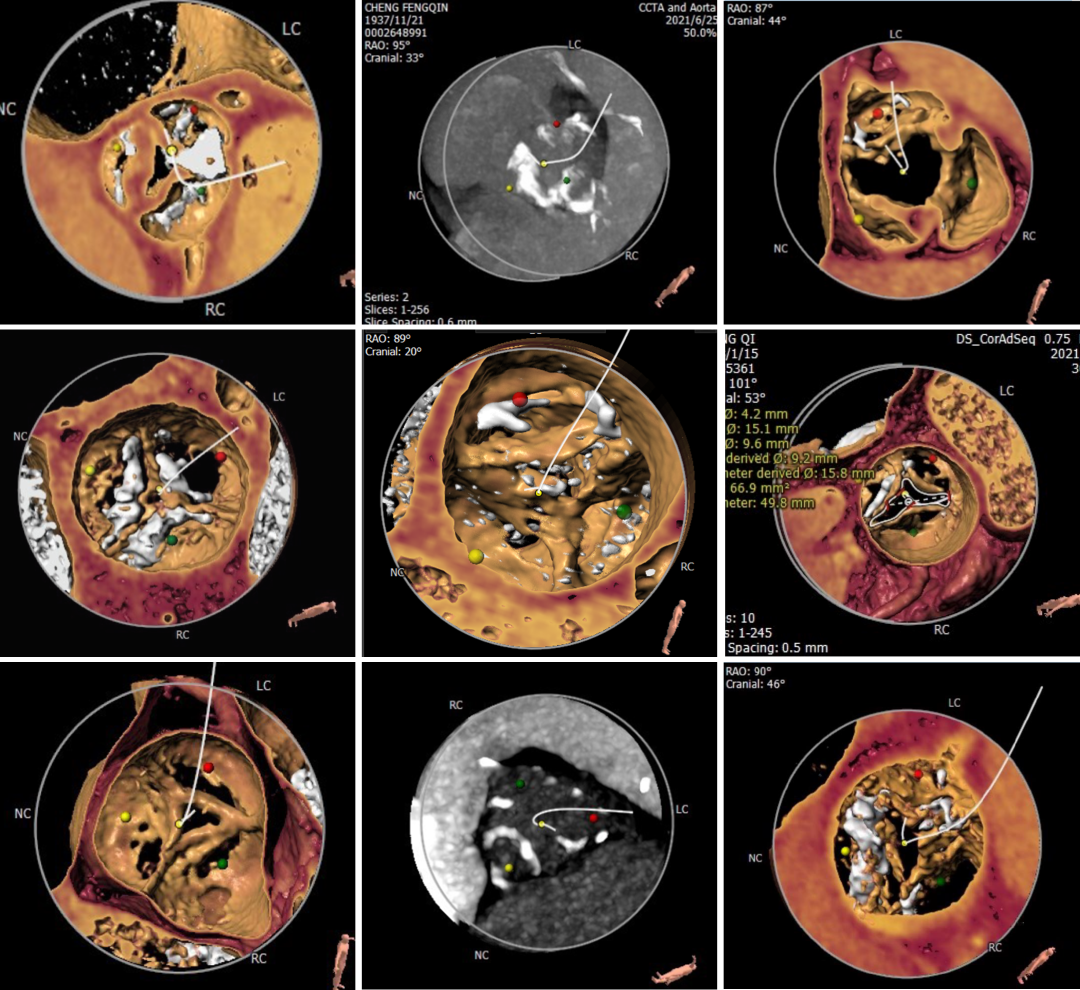

为期两天的手术联播过程中,来自厦门大学心血管病医院王斌教授,首都医科大学附属北京安贞医院宋光远教授,阜外华中心血管病医院王圣教授,南京医科大学第一附属医院孙伟教授,广东省人民医院李捷教授,中国医学科学院阜外医院吴永健教授,中南大学湘雅二医院方臻飞教授,浙江大学医学院附属第二医院王建安教授,北京大学第三医院唐熠达教授分别带来了精彩的TAVR实战案例。

从三叶瓣重度钙化到二叶瓣畸形的根部解剖,从单纯主动脉瓣反流到入路极端迂曲挑战的案例。TaurusOne凭借其优异的柔顺性,支撑力强及内外层双侧裙边的特点,都能从容应对复杂的临床患者解剖结构。从患者的临床选择到术后的长久获益,从手术入路的种类到术中操作的注意事项,从围术期卒中的循证医学到术后的抗凝抗栓用药规范,在线专家共同交流彼此中心的围术期TAVR经验和分享现阶段经导管主动脉瓣置换的诊疗策略。针对当前TAVR领域多个热点学术问题进行了热烈的讨论,现场可谓精彩纷呈、高潮迭起。专家们纷纷借此契机相互交流探讨,分享各自的单中心经验,力求进一步提升TAVR手术的安全性和有效性,为主动脉瓣相关疾病的患者带来长远综合获益。